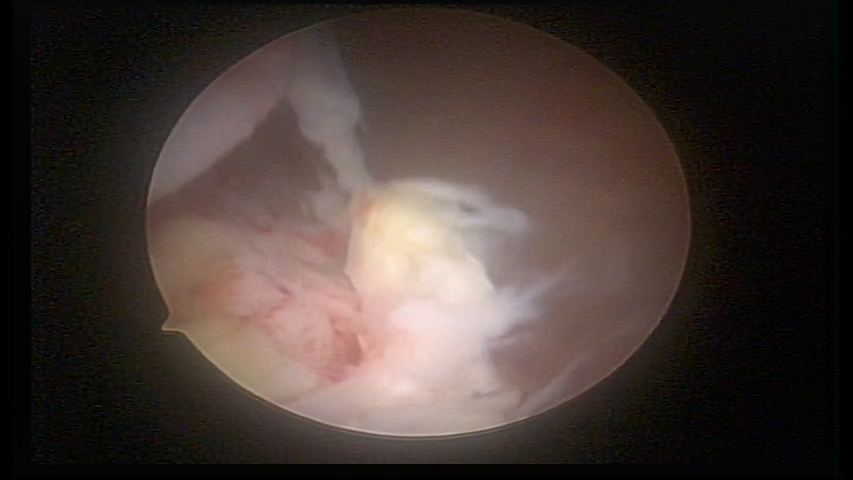

Material Trofoblástico retido

Material Trofoblástico

METAPLASSIA ÓSSEA